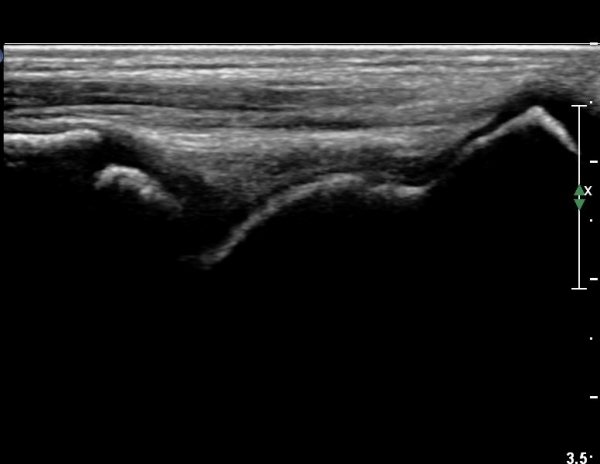

¼ºº° / ³ªÀÌ

³²Áö/ 7¼¼

ÁÖÁõ»ó

¿ìÃø ¹ß¸ñÀÇ ÅëÁõ(1ÀÏ)

º´·Â

ÇÏ·ç Àü ¹ß¸ñÀ» »ß´Ù

ÀÌÇÐÀû °Ë»ç

Àü°ÅºñÀÎ´ë ºÎÀ§ ±¹¼ÒÀû ¾ÐÅë, ºÎÁ¾À» º¸ÀÓ. Àü¹æ´ç±è°Ë»ç (+)

ÃÊÀ½ÆÄ °Ë»ç